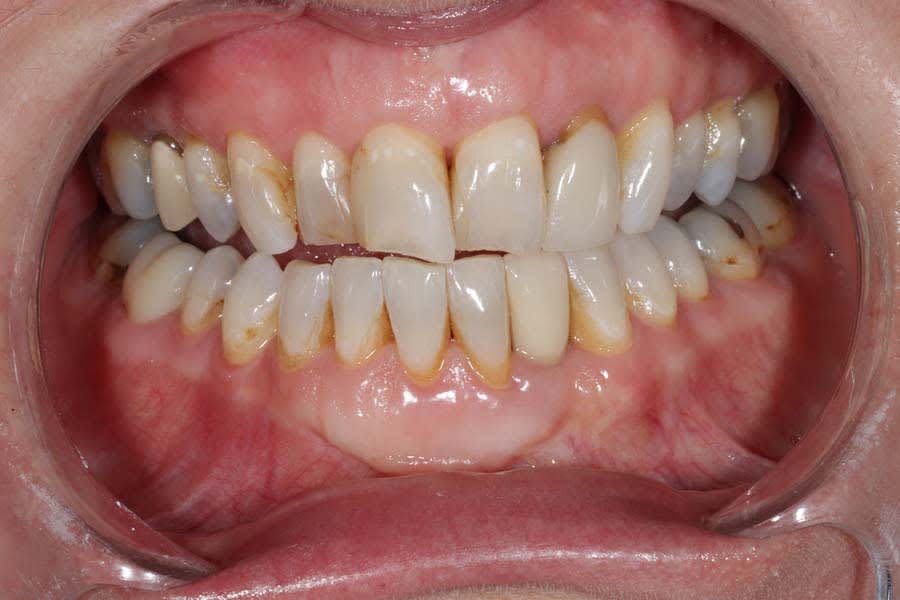

The patient expressed worry about further tooth fractures and dissatisfaction with anterior tooth wear and chipping (Figure 1 and Figure 2). She sought esthetic smile improvement and a comprehensive plan to prevent further breakdown and was open to a systematic approach to data gathering for diagnoses and planning. Historically reliant on single-tooth dentistry, she embraced a thorough approach that involved orthodontics and restorative care to address occlusal and esthetic issues.

Clinical examination identified large restorations (>1/3 intercuspal width) and wear patterns not reported in her dental history questionnaire. Notably, anterior tooth wear was evident, but the patient felt that the wear had not changed in the past 5 years, which was supported by a 12-year historical photograph. This suggested that the occlusal damage could be a result of previous adaptation rather than active breakdown. The report of clenching, however, indicated an ongoing problem, requiring a joint-based reference position.

Functional: Moderate anterior attrition (1 mm to 1.5 mm) was noted, particularly on teeth Nos. 6 through 9 and 24 through 27, with no significant posterior wear or abfraction lesions. The patient reported slow progression of attrition on her front teeth that had stabilized over the past 5 years, corroborated by a historical photograph. Temporomandibular joint (TMJ) evaluation revealed a 40 mm maximum opening with slight right deviation, asymmetrical lateral movements (8 mm right and 11 mm left), and no pain or joint sounds. She had facial asymmetry as her chin point was 2 mm right of center. CBCT imaging showed a non-reducing anteriorly displaced disc in the right TMJ with osteophyte formation and reduced cortical bone, contrasting a normal left TMJ (Figure 6). Occlusal dysfunction was suspected due to her aberrant chewing pattern, which resulted in unilateral attrition and clenching. Her initial deprogramming identified the first contact on tooth No. 2 with a slide into maximum intercuspation, supporting an occlusal dysfunction diagnosis.

Dentofacial: The patient expressed concerns about mismatching tooth color, shape, and position. Her lip moved 10 mm from repose to Duchenne smile, placing her in the high end of normal range (6 mm to 10 mm).3 Gingival margins were uneven with supraeruption present resulting in a diagnosis of dentoalveolar extrusion with wear.4 Tooth rotations and overlaps were present as was a “black triangle,” ie, missing papilla, between teeth Nos. 9 and 10 due to the 6.8 mm distance between the crestal bone and contact point (Figure 7 and Figure 8).5 Pronounced negative buccal corridors were evident. Gingival tissue was displayed while smiling, giving the patient a high-risk dentofacial diagnosis.